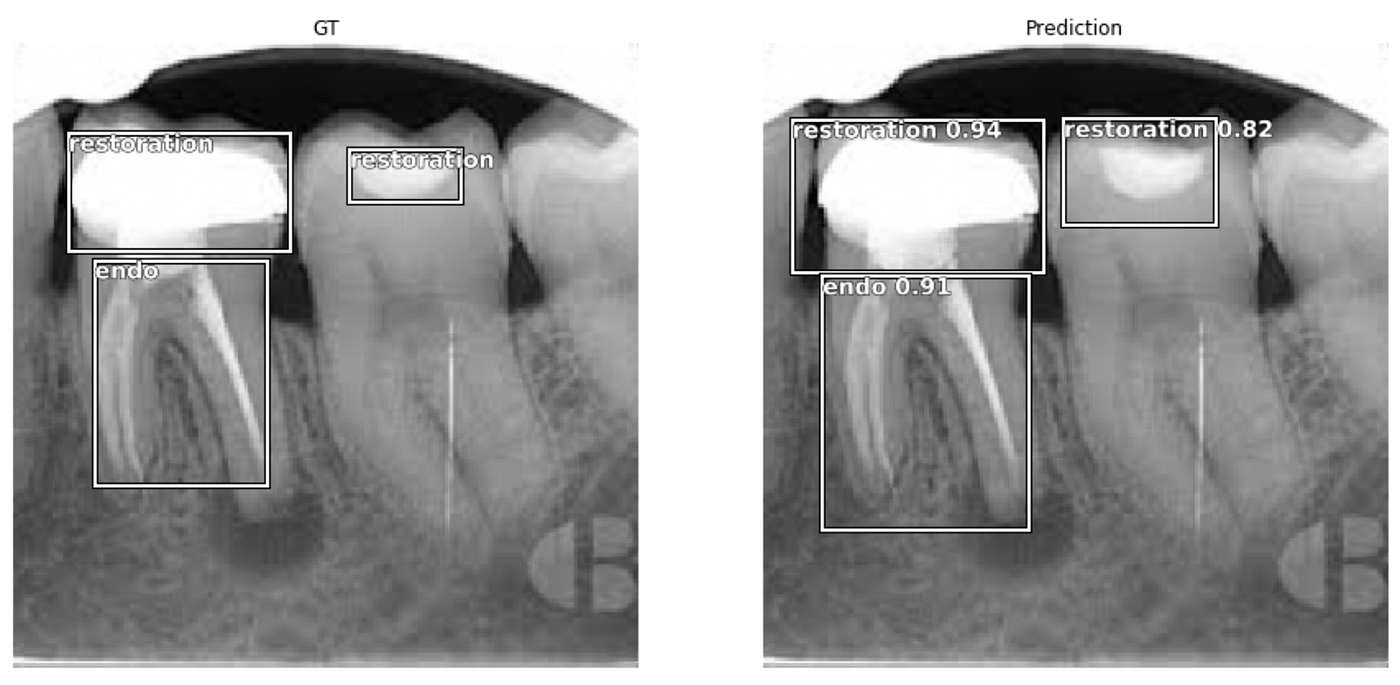

Fastai Object Detection Applied To Dental Periapical X-rays By John Persson Analytics Vidhya Medium